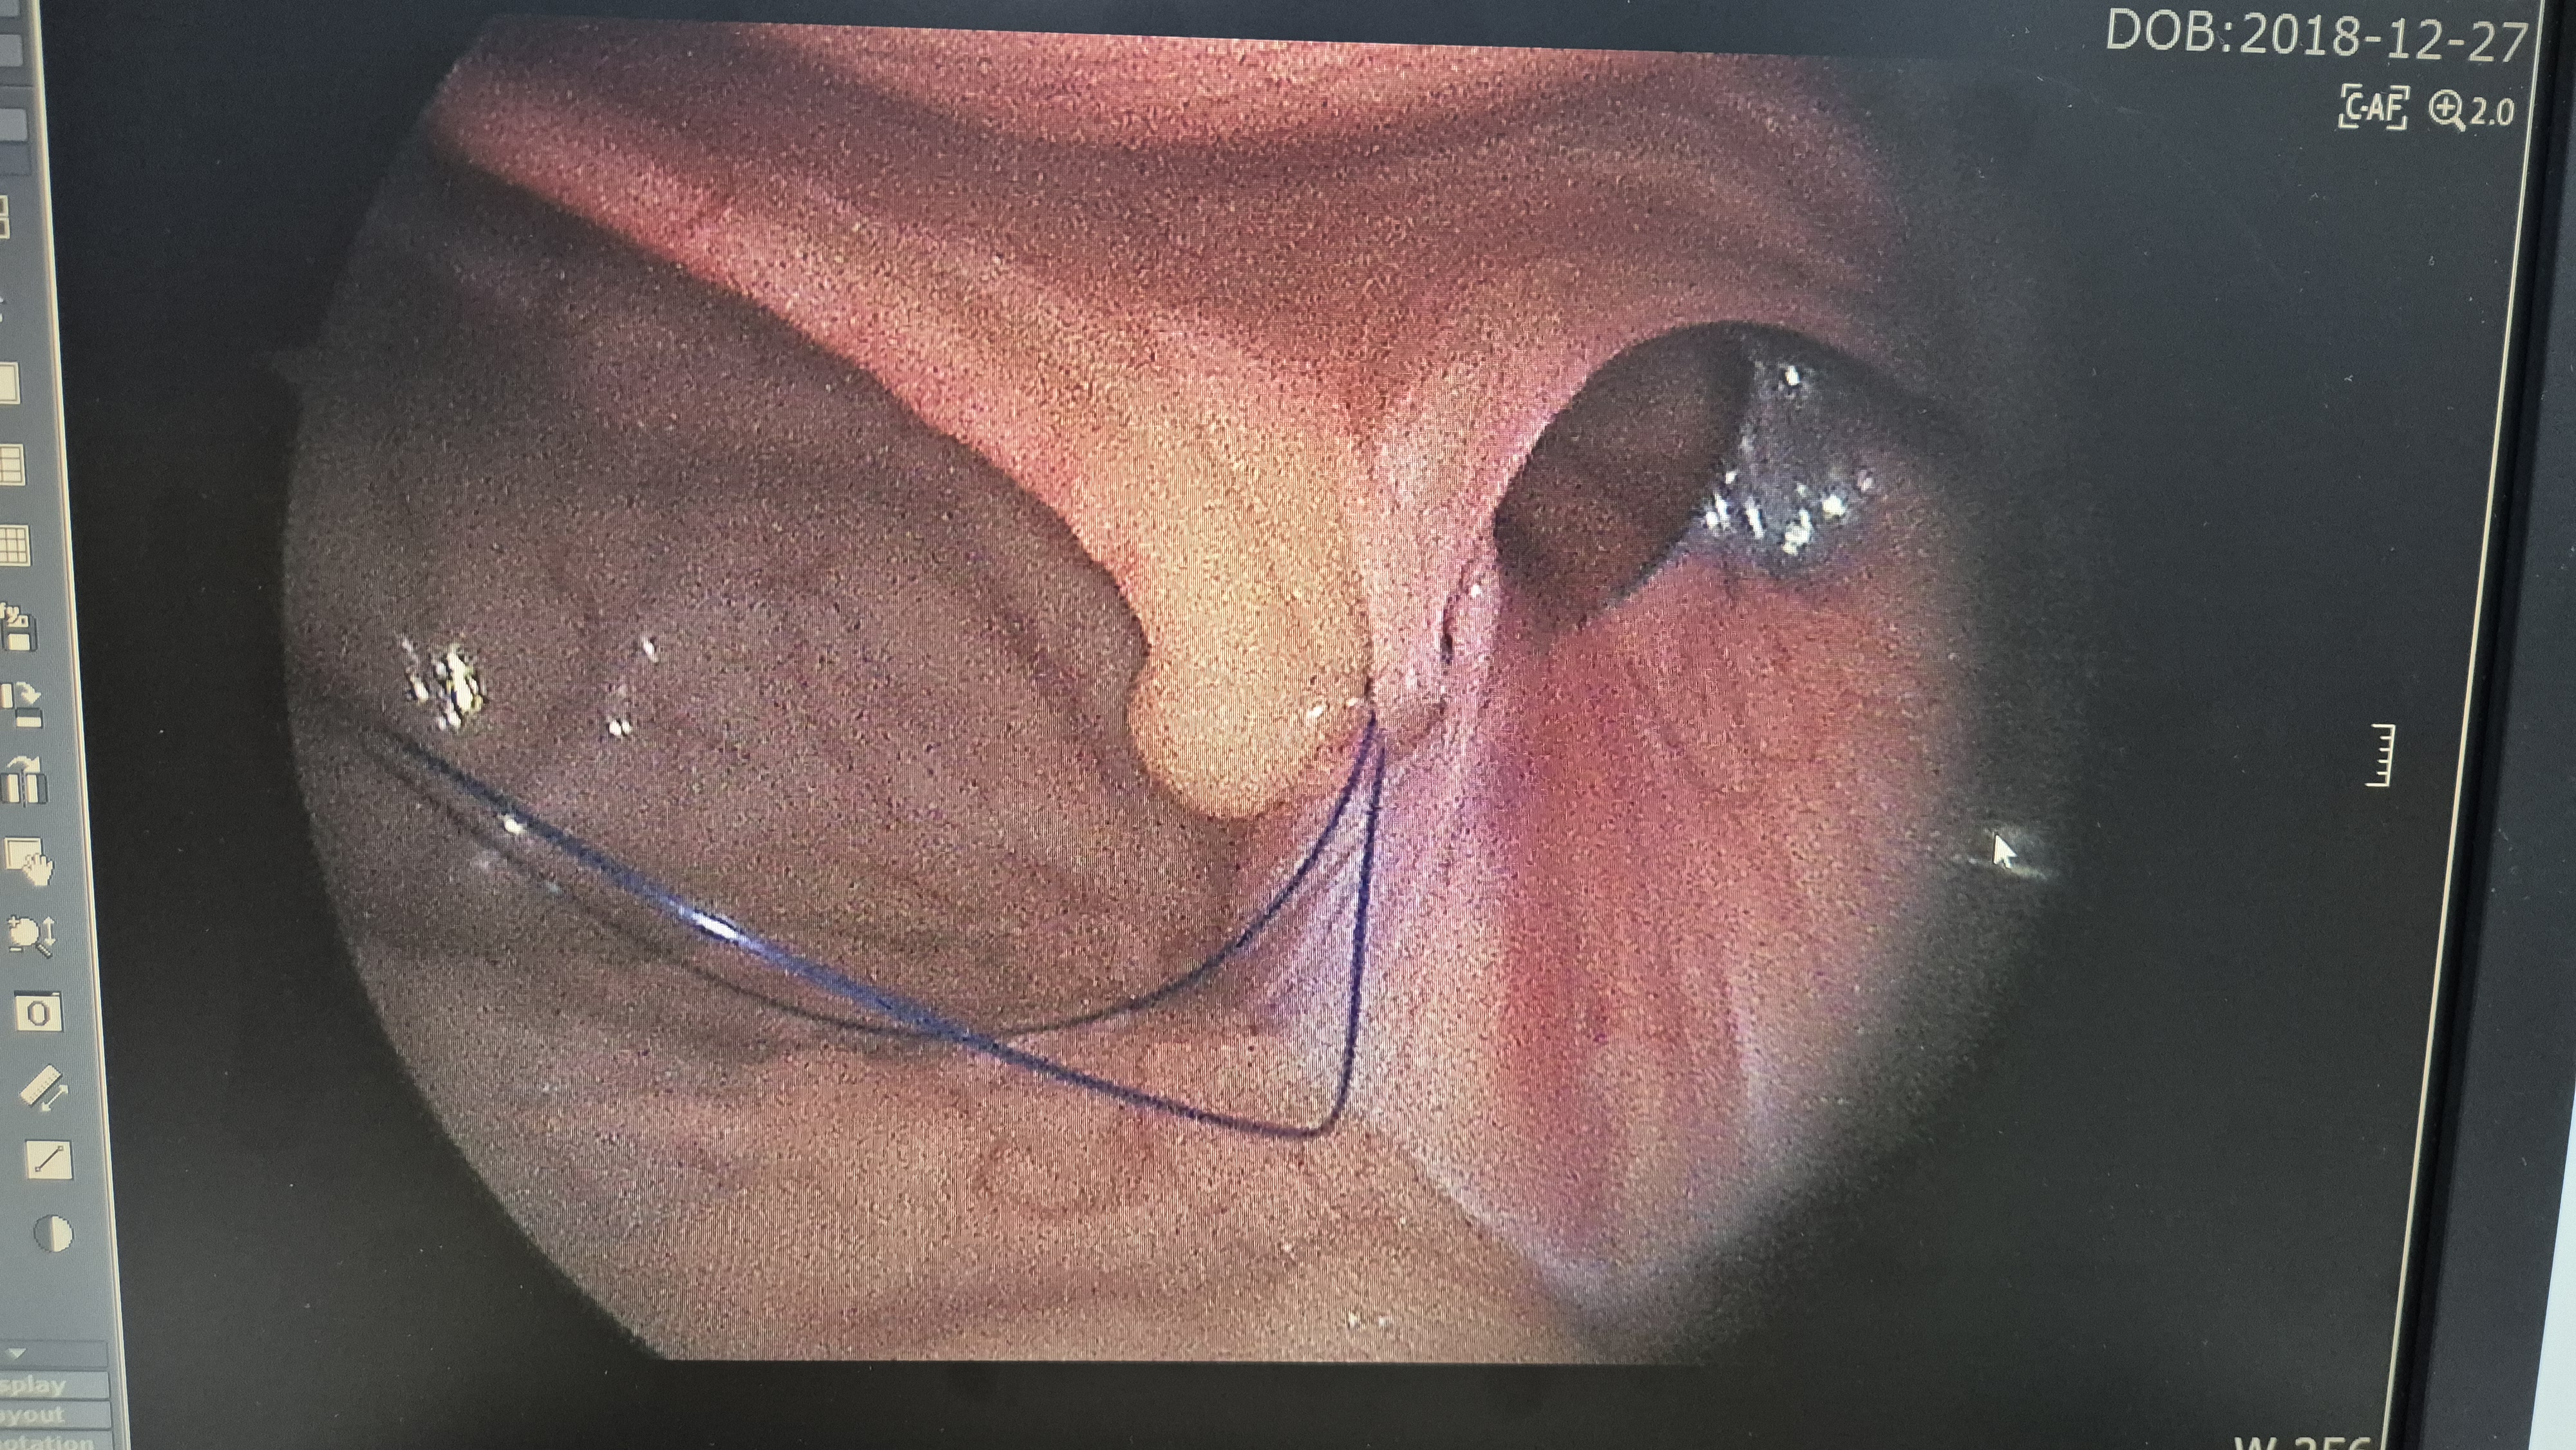

탈장 교정중.

교정후.